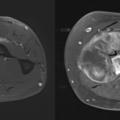

Prise en charge chirurgicale des sarcomes des tissus mous

La chirurgie est la pierre angulaire du traitement des sarcomes des tissus mous (STM). La survie globale des STM dépasse les 70 % à cinq ans ; elle est en amélioration constante d’année en année grâce à une meilleure prise en charge.1,2 La qualité de la chirurgie conditionne la survie globale en cas de sarcome tronculaire…